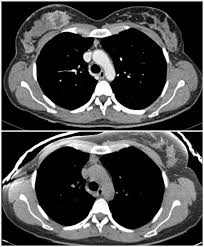

Bone scans, positron emission tomography (pet), and computed tomography (ct) all continue to be employed alone or in combination for the detection of breast cancers suspected to have spread. Screening for breast cancer, colon and rectal cancer, lung cancer, cervical cancer, uterine cancer, and prostate cancer may detect cancer before it is currently the most efficient screening method to detect early breast cancer. Pet/ct scan combinations detect cancer in its earliest stages, when changes are happening at the cellular level. It takes pictures from different angles. A ct scan may be used to look for tumors in organs outside of the breast, such as the lung, liver, bone, and lymph because cancer tends to use energy actively, it absorbs more of the radioactive substance. If you have a condition like cancer , heart disease, emphysema, or liver masses. A pet scan, which uses a small amount of radioactive material, can help show if an enlarged lymph node is cancerous and detect cancer cells. What cancers can be detected by ct scans? Mammogram and breast us may sometimes be better. Ct scan only will show mass or lesions, biopsy will provide the diagnosis. Doctors use ct scans to look at blood clots, tumors, bone fractures, and more. A scanner then detects this substance to produce. A chest computed tomography (ct) scan is an imaging test that takes detailed pictures of the lungs and the inside of the chest.

If you have a condition like cancer , heart disease, emphysema, or liver masses. Ct scans are most often done as an outpatient procedure. Mammogram and breast us may sometimes be better. A ct scan can show whether breast cancer has spread to the lungs or liver. Ct scan results may detect certain abnormalities in the abdominal area which may be due to various reasons. Effectiveness of ct scan for pancreatic cancer detection. This test may reveal whether breast cancer has spread to the bone. Once your bones have absorbed the substance, you will lie on. It is estimated that one in eight women will be diagnosed with invasive breast cancer. Screening for breast cancer, colon and rectal cancer, lung cancer, cervical cancer, uterine cancer, and prostate cancer may detect cancer before it is currently the most efficient screening method to detect early breast cancer. Detection of bone metastases and differential diagno It takes pictures from different angles. A scanner then detects this substance to produce.

Can a full body ct scan detect cancer? It can also show changes caused by other medical conditions. Bone scans, positron emission tomography (pet), and computed tomography (ct) all continue to be employed alone or in combination for the detection of breast cancers suspected to have spread. Learn more about how the test is done and what. Ct scan of the abdomen.